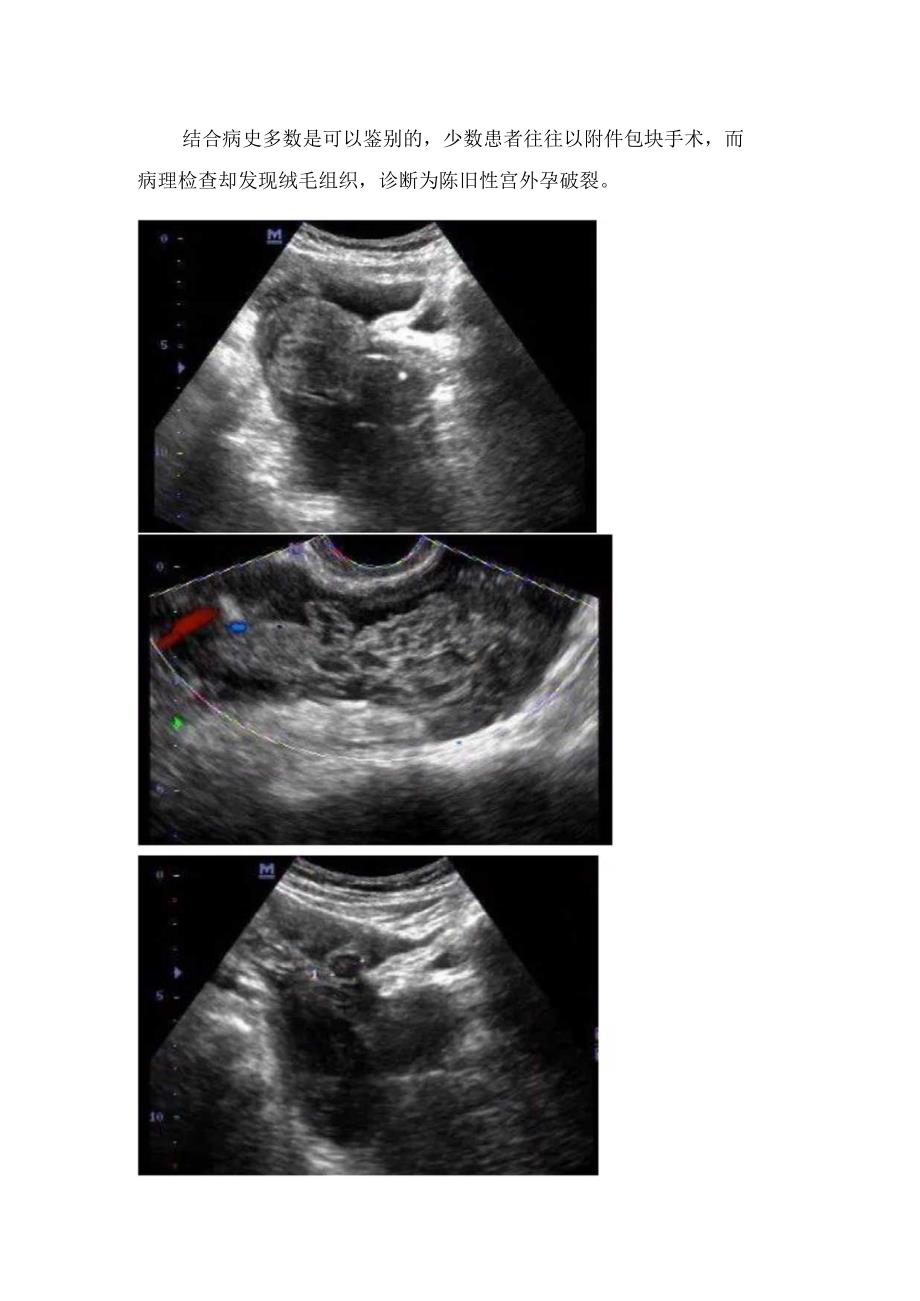

4、有闭经史,尿HCG阳性。超声鉴别经验宫外孕与黄体破裂在临床及其他检查方面没有明显的特异性,往往出现误诊或漏诊。在检查时细致分析,两者表现仍有所区别:黄体破裂超声表现以盆腔液体为主,附件区包块较少;而宫外孕超声表现以附件分布不均匀的杂乱的混合回声包块伴盆腔游离液体为主,这是由于异位的妊娠囊破裂口有反复出血,以后孕卵死亡,内出血停止形成肿块,凝血块机化,与周围组织粘连甚至包裹所致。结合病史多数是可以鉴别的,少数患者往往以附件包块手术,而病理检查却发现绒毛组织,诊断为陈旧性宫外孕破裂。1.THIlI川IillHhIlIiIInhlIIInIlllInllIllIllIlIlIIIIIilII二,黄体破裂